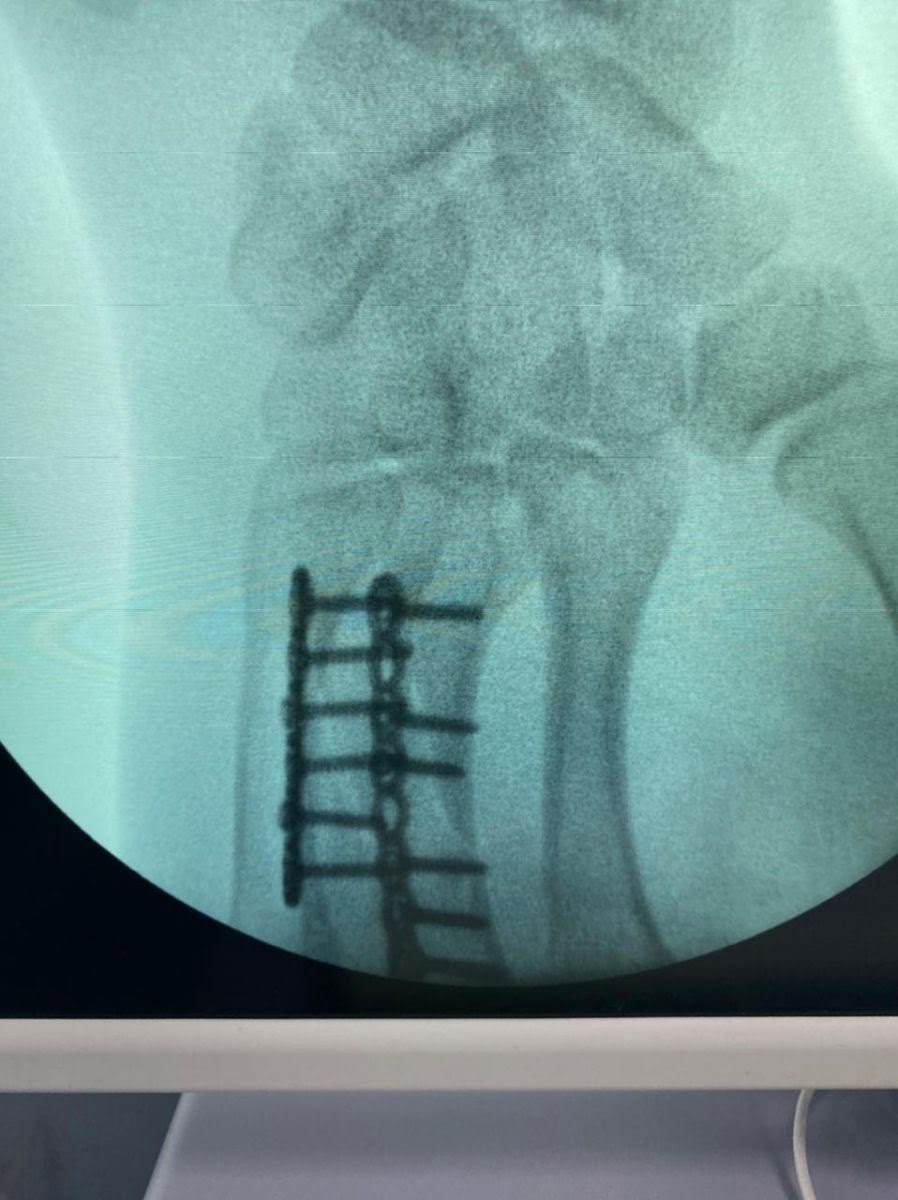

Наталья Непряева прооперирована в АНО ЦКБ Святителя Алексия Митрополита Московского, руководителем центра микрохирургии кисти, реконструктивной и пластической хирургии, к.м.н., доцент кафедры травматологии и ортопедии РНИМУ им. Пирогова - Калантырской Валентиной Анатольевной. Была выполнена реконструкция пястных костей 3 и 4 пальцев правой кисти при помощи специальных пластин. Сроки восстановления около 3-4 недель. После осмотра врача 1 февраля Наталья планирует свое возвращение в команду.